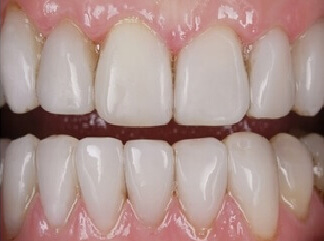

Probleem. Hambakivi on nähtav hambapindadel.

Lahendus. Protseduuri käigus eemaldatakse hambapindadelt hambaplaak, kasutades ultraheli-skaalerit ja tahmapuhurit (“Air Flow”). Protseduuri lõpus hambad poleeritakse.